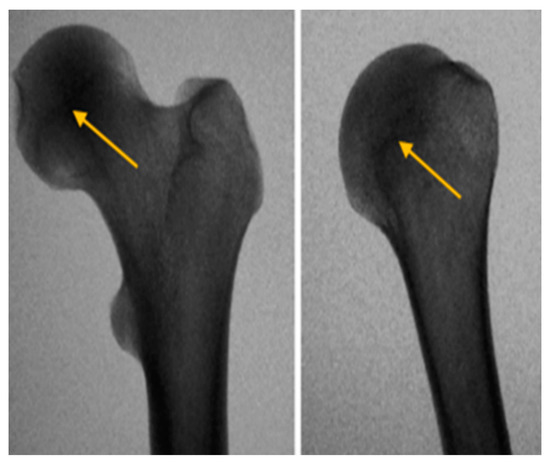

Radiological investigations were carried out to exclude the presence of gunshot ammunition material, to exclude further microfractures and to determine the degree of fusion of the ossification nuclei (Figure 6) and, finally, several soft tissue samples were taken, where possible, for histological and genetic investigations. The samples taken were subjected to DNA extraction using the commercial NucleoSpin®DNA Tissue kit from MACHEREY-NAGEL, following the specific protocol indicated by the manufacturer.

Figure 6. Analysis of the degree of fusion of ossification nuclei of the proximal epiphysis of the femur and humerus.